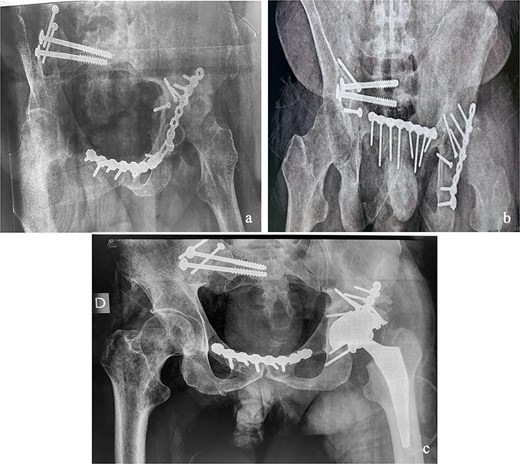

This was a 42-year-old male patient with no previous medical history who was admitted to the intensive care unit for treatment of polytrauma: severe chest trauma and pelvic trauma. During his stay in intensive care, the patient developed a pulmonary infection complicated by septicemia, requiring prolonged antibiotic therapy and thereby contraindicating any internal surgical fixation. After hemodynamic and respiratory stabilization, he was transferred to our department 40 days after the trauma with the following injuries: an unstable pelvic ring fracture classified as Tile-AO B1-2 [4]: disjunction of the pubic symphysis, disjunction of the right sacroiliac joint, and an ipsilateral crescent fracture classified as Kumar-Day 2 [5], along with a transverse–posterior wall fracture of the left acetabulum associated with a posterior dislocation of the hip, which was initially reduced but remained unstable. Fixation was performed using a Hoffmann II external fixator applied to the iliac crests with poor reduction (Fig. 1). He presented with complete weakness of the left foot dorsiflexors, with preserved sensation and no urogenital or abdominal complications. ORIF was performed in two stages, 5 days apart. The first stage consisted of performing the first two windows of the ilioinguinal approach: the lateral window to access the sacroiliac joint and the middle window to access the lower part of the sacroiliac joint and remove the osteofibrous callus. A Pfannenstiel approach was used to remove the callus at the pubic symphysis and fix it with a plate. The patient was then placed in the prone position and a posterior approach to the right sacroiliac joint was performed to carry out the same procedures on the posterior part of this joint and to perform fixation using ilioiliac and iliosacral screws. The second stage of the operation involved acetabular surgery. Given the chronic dislocation of the left hip, an anterior approach to the hip was performed to remove the intra-articular fibrosis facilitating the subsequent reduction of the femoral head. A Kocher-Langenbeck approach was then performed to remove the callus, reduce the femoral head and fracture, and fix it with a plate (Fig. 2). Postoperatively, the patient retained neurological deficits. At 6 months, the patient was able to walk without assistance and had a Harris Hip Score (HHS) score of 80 and Majeed score of 75 [6, 7].

Immediate postoperative X-rays. (a) Anteroposterior pelvic X-ray. (b) Inlet view of the pelvis. (c) Alar oblique view of the pelvis. (d) Obturator oblique view of the pelvis.